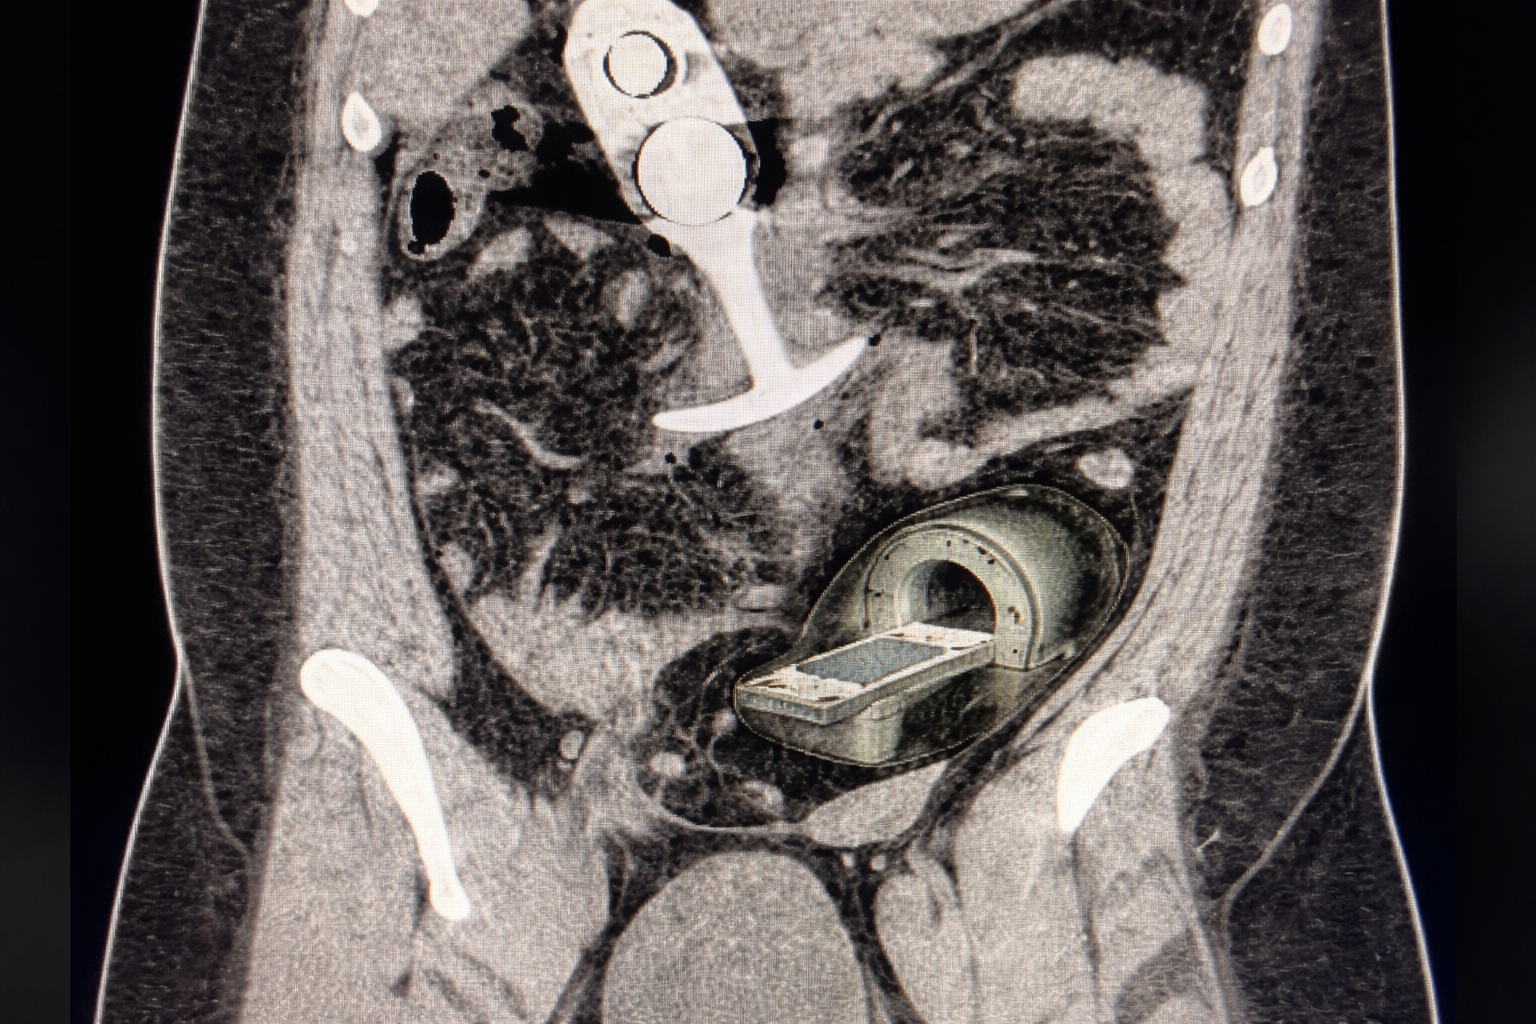

Uma paciente sofreu um episódio doloroso — e altamente constrangedor — ao realizar um exame de ressonância magnética após manter um objeto com componente metálico no interior do corpo. Durante o procedimento, o item foi violentamente atraído pelo campo magnético, deslocando-se com força e causando lesões internas.

No caso relatado, a paciente foi questionada previamente, mas acreditava que o objeto utilizado era composto apenas de silicone. No entanto, havia uma estrutura metálica interna, que reagiu imediatamente ao campo magnético.

Segundo registros, o objeto se deslocou rapidamente em direção à região torácica. Apesar da gravidade da situação, não houve danos extensos. Ainda assim, a paciente apresentou dor intensa, náuseas e sinais de desmaio, sendo encaminhada ao hospital para atendimento.

O episódio ganhou repercussão após a divulgação de uma imagem do exame, gerando forte reação nas redes sociais.